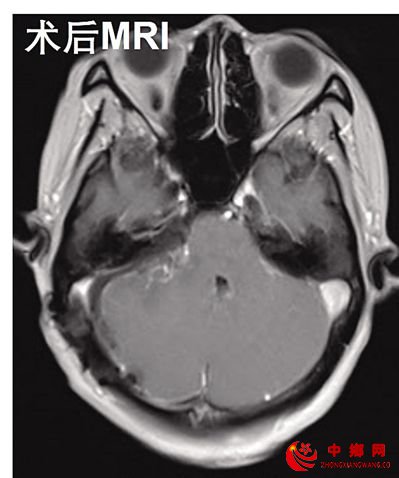

转机的来到是因为一次持续性头痛。在来到重医附二院就诊后,神经外科主任谢宗义详细地了解了杨丁的病情和既往病史,在向患者解释听力下降除了考虑耳部的病变外,还需排查听力传导通路(位听神经)相关的颅内病变。在进行了头部CT、MRI等相关检查后,发现杨丁右侧桥小脑角区占位长了听神经瘤。

“医生告诉我,我的肿瘤血供极其丰富,并且严重压迫脑干,还与脑干粘连紧密。手术的难度和风险非常高。”尽管手术的难度大、风险高,但病情已经到了非做手术不可的地步。经过充分的术前准备和评估,杨丁的手术由神经外科程远教授和谢宗义主任主刀,所幸,全切肿瘤手术十分成功。